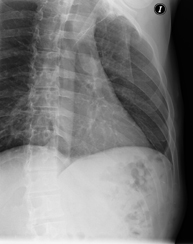

- RX Tòrax

Tècnica que usa els raigs X a través de la qual s'obtenen imatges de la caixa toràcica (cor, pulmó, arcs costal, clavícules, etc.) per al seu estudi. - RX Ester

Tècnica que usa els raigs X a través de la qual s'obtenen imatges dels sins paranasals per al seu estudi. Indicacions: cefalea, tos crònica. - RX Tòrax

Una radiografia de tòrax és una tècnica mitjançant la qual, amb l'ús d'una petita dosi de radiació, s'obté una imatge bidimensional de la caixa toràcica i el seu contingut (pulmons, cor, mediastí, etc. ). És una de les proves mèdiques realitzades més comuna. - RX Abdomen